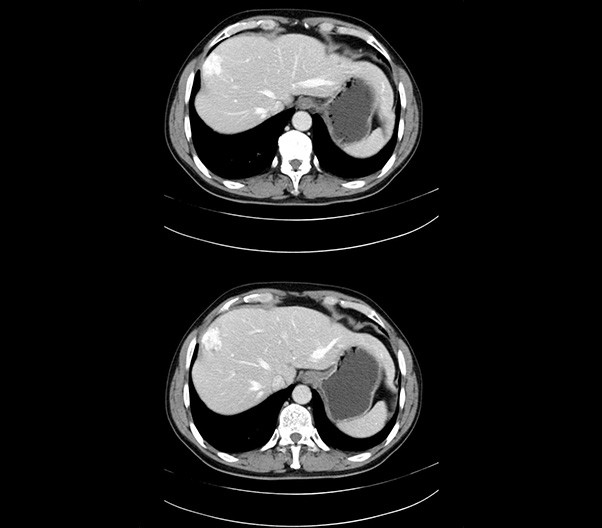

The 1024-pixel image matrix brings superior image clarity (0.6 mm slice thickness) and stimulates the early detection of small lesions, thus improving diagnostic reliance.

ScintCare CT 16 incorporates an entirely digital integrated ScintiStar detector, which was solely developed by MinFound, from material to the whole structure design, based on the technical know-how of our skilled scientific team. The system produces high-resolution images with a low radiation dose and an excellent signal-to-noise ratio.